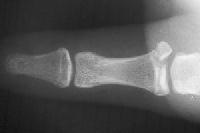

Not all need repair. This patient had an injury associated with rotation of the avulsion fracture. This often indicates a combination of fracture and ligament tear. However, the joint was stable, and had a good result from splinting alone. The bottom film shows the expected asymptomatic fibrous nonunion.